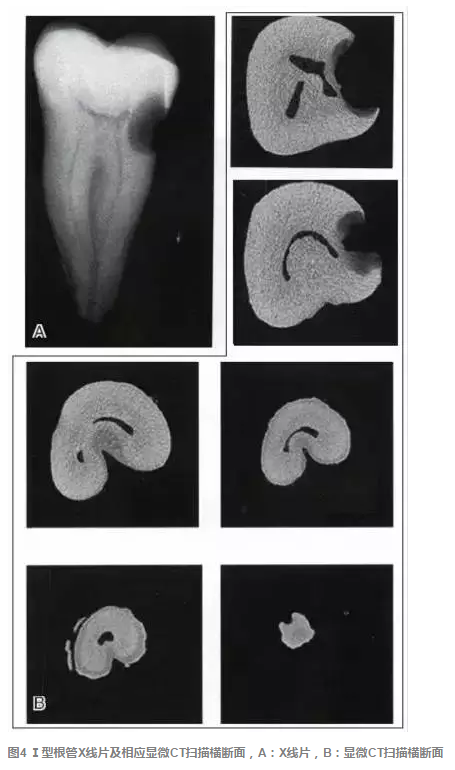

傳統(tǒng)的Melton C形根管分類法雖深化了對根管結(jié)構(gòu)的認識,但由于是基于組織學(xué)的分類,不能指導(dǎo)臨床實踐。有學(xué)者基于C形根管X 線特征,結(jié)合顯微CT掃描結(jié)果,提出了一種新的分類方法,便于臨床應(yīng)用。這種分類方法將下頜第二磨牙分為3型:①Ⅰ型:融合型,X線片上見2個根管,但在根尖區(qū)融合;②Ⅱ型:分離型,X線片上見2個根管且相互獨立;③ Ⅲ型:不對稱型,X線片上雖有2個根管相互獨立,但一長一短,互不對稱(圖3)。各類型C形根管X線特征、顯微CT掃描及重建結(jié)果見圖4~9。

圖1 下頜第二磨牙C形根管系統(tǒng)的形態(tài)從根管口到根尖(A~H)可發(fā)生巨大變化